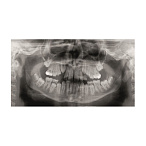

Цифровой панорамный томограф Gendex Pan eXam Plus 2D — это современное и надежное решение для оснащения стоматологической клиники или кабинета. Аппарат предназначен для получения высококачественных двухмерных панорамных снимков зубных рядов, что является основой для планирования лечения, имплантации, ортодонтической коррекции и оценки общего состояния зубочелюстной системы.

Качество изображений и диагностические возможности

Качество снимка — главный критерий выбора диагностического оборудования.

- Высокое разрешение и детализация: Цифровой датчик обеспечивает четкие и контрастные изображения с отличной визуализацией костной структуры, корней зубов, состояния пародонта и нижнечелюстного канала.

- Широкий набор программ сканирования: Аппарат поддерживает различные режимы съемки, адаптированные под конкретные клинические задачи: стандартная панорама, панорама детей, съемка височно-нижнечелюстных суставов (ВНЧС), синус-сканирование и другие.